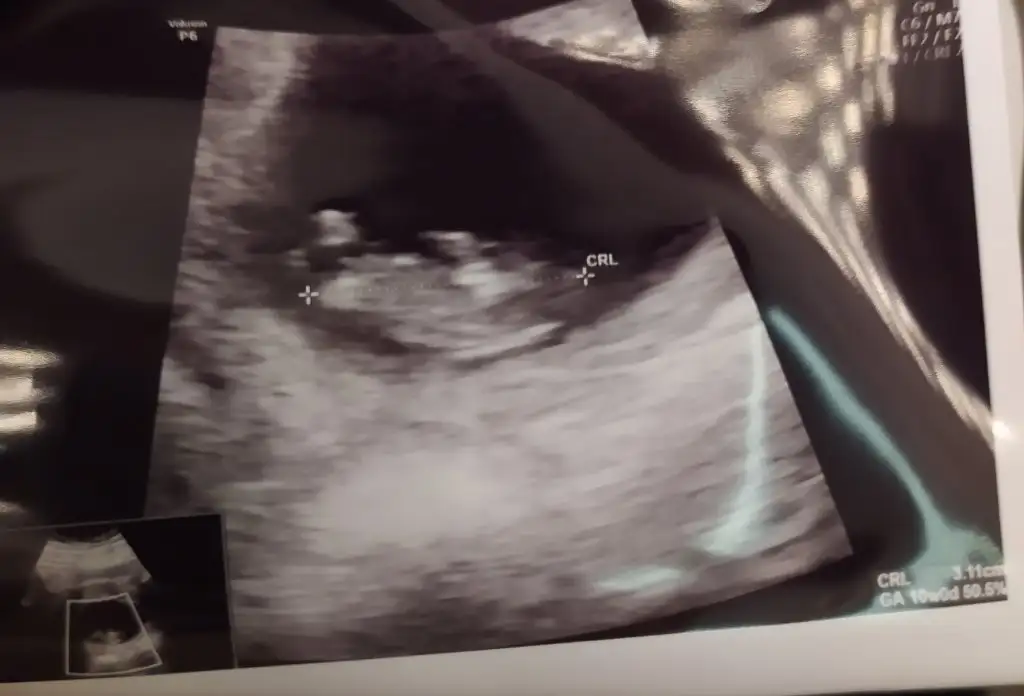

Merhaba, 13.hafta ultrason görüntüsüne göre cinsiyet tahmini yapabilir misiniz?cinsiyeti ogrenebildiz mi ? Allah sağlıkla büyütmek nasip etsin.. benim bebeğim de 11 haftalık çok merak ediyorum yorumlar misinizzz

Benimde 13 haftalık ikili taramada erkege benzettim dedi ama görüntü net degil keseden anlayan cıkarmıMerhaba, 13.hafta ultrason görüntüsüne göre cinsiyet tahmini yapabilir misiniz?